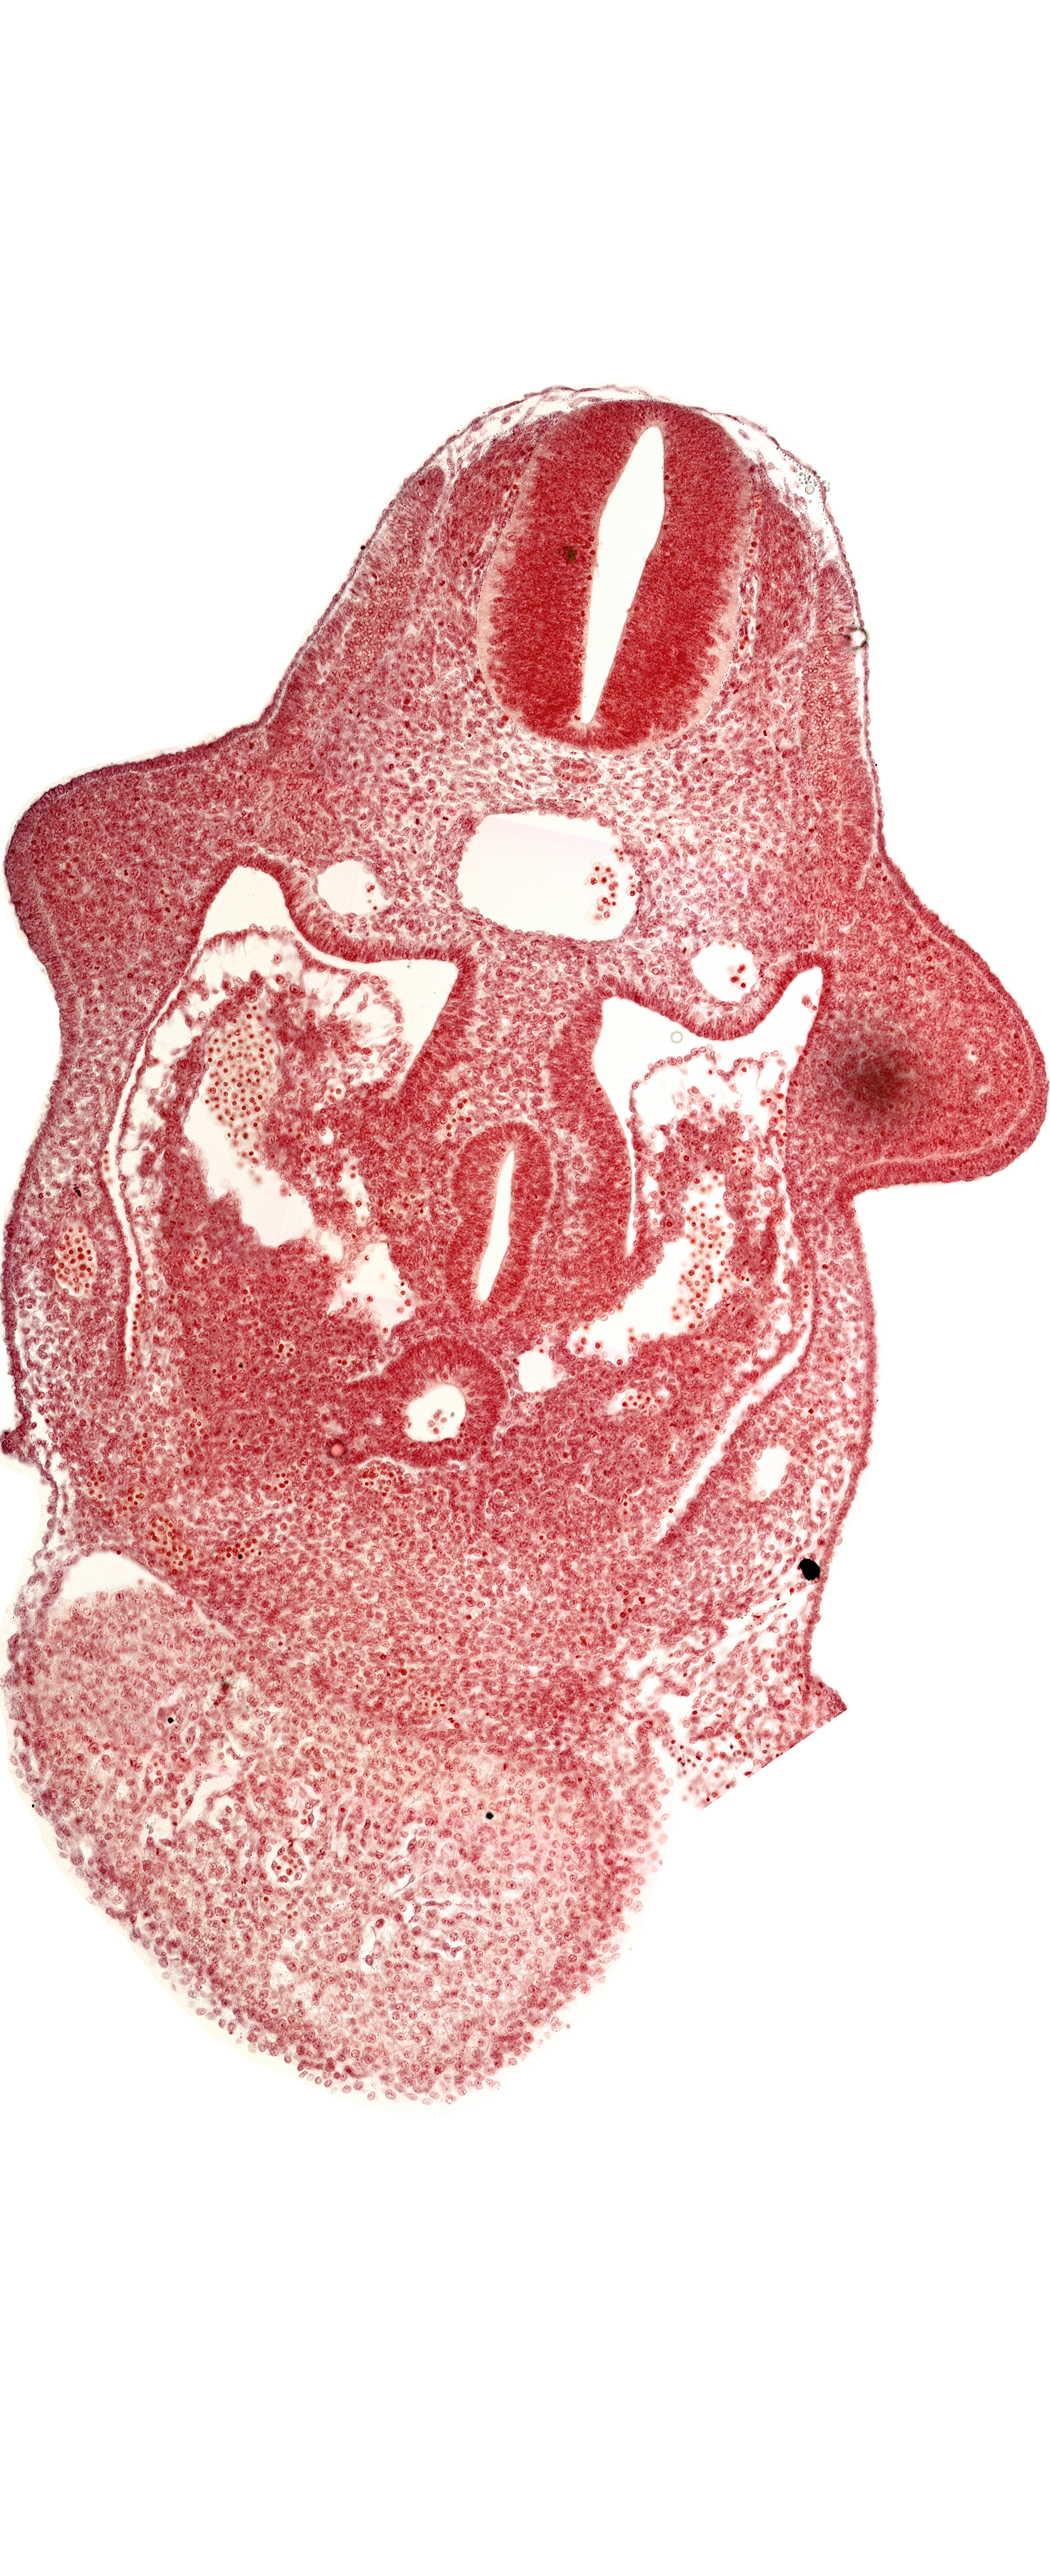

alar plate(s), amnion attachment, basal plate, coelomic cavity, common aorta, common ventricle, dorsal pancreatic bud, duodenum primordium, hepatic antrum, hepatocardiac vein, left umbilical vein, postcardinal vein, septum transversum, upper limb bud

Carnegie Embryo #836   |   Location: 08-03-05

Keywords: alar plate(s), amnion attachment, basal plate, coelomic cavity, common aorta, common ventricle, dorsal pancreatic bud, duodenum primordium, hepatic antrum, hepatocardiac vein, left umbilical vein, postcardinal vein, septum transversum, upper limb bud